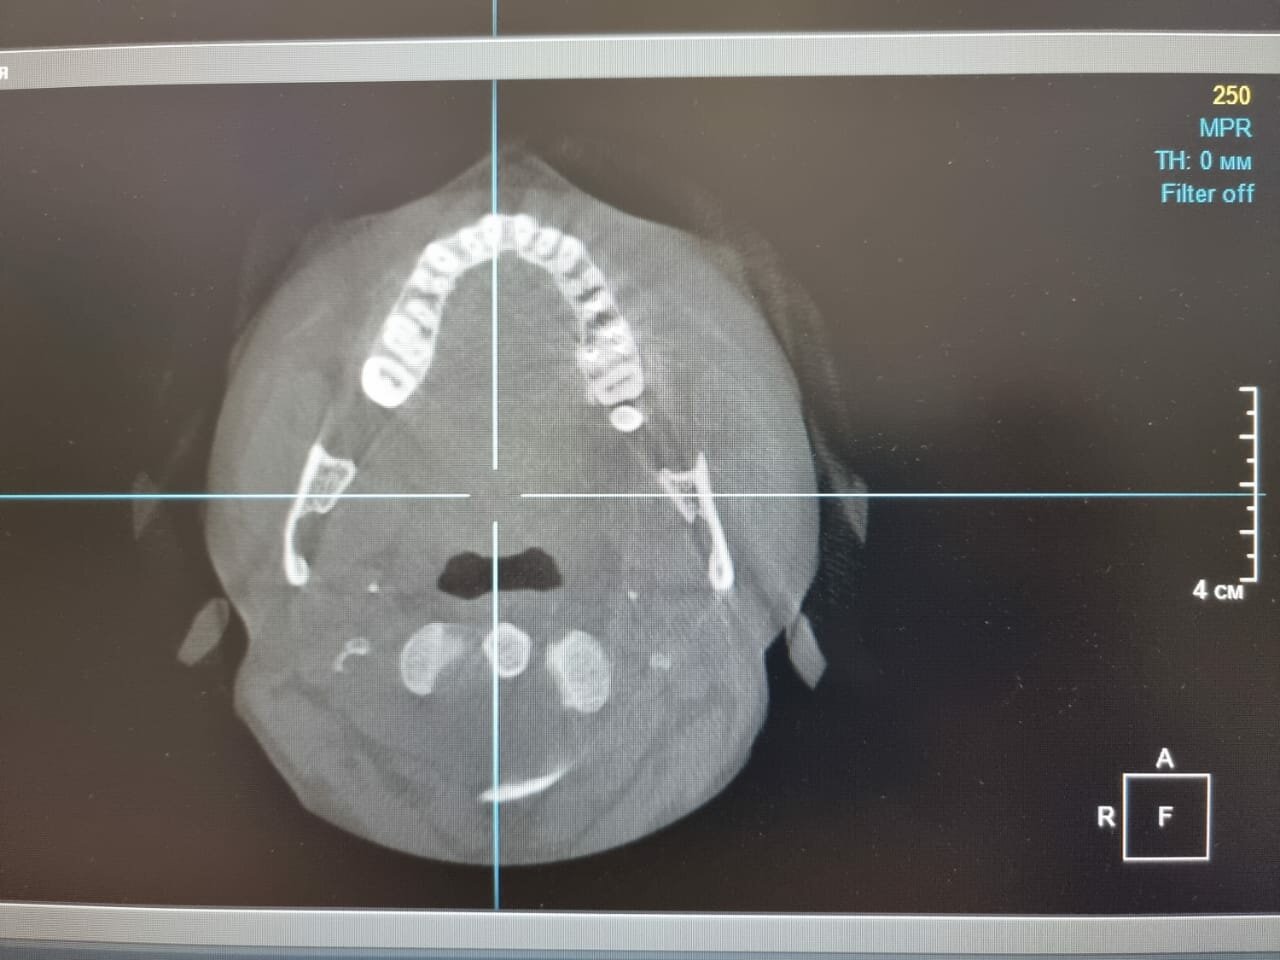

Основные направления работы клиники: общая стоматология (лечение кариеса, гигиена, удаление зубов), ортодонтия (брекеты, элайнеры), хирургическая стоматология (имплантация, челюстно-лицевые операции), эстетическая стоматология (виниры, отбеливание, реставрация) и детская стоматология. В клинике используются передовые технологии, включая лазерную стоматологию, компьютерную томографию и цифровую диагностику, что обеспечивает безболезненное и эффективное лечение.

- рентгенография

- Современное оборудование и качественный ремонт.